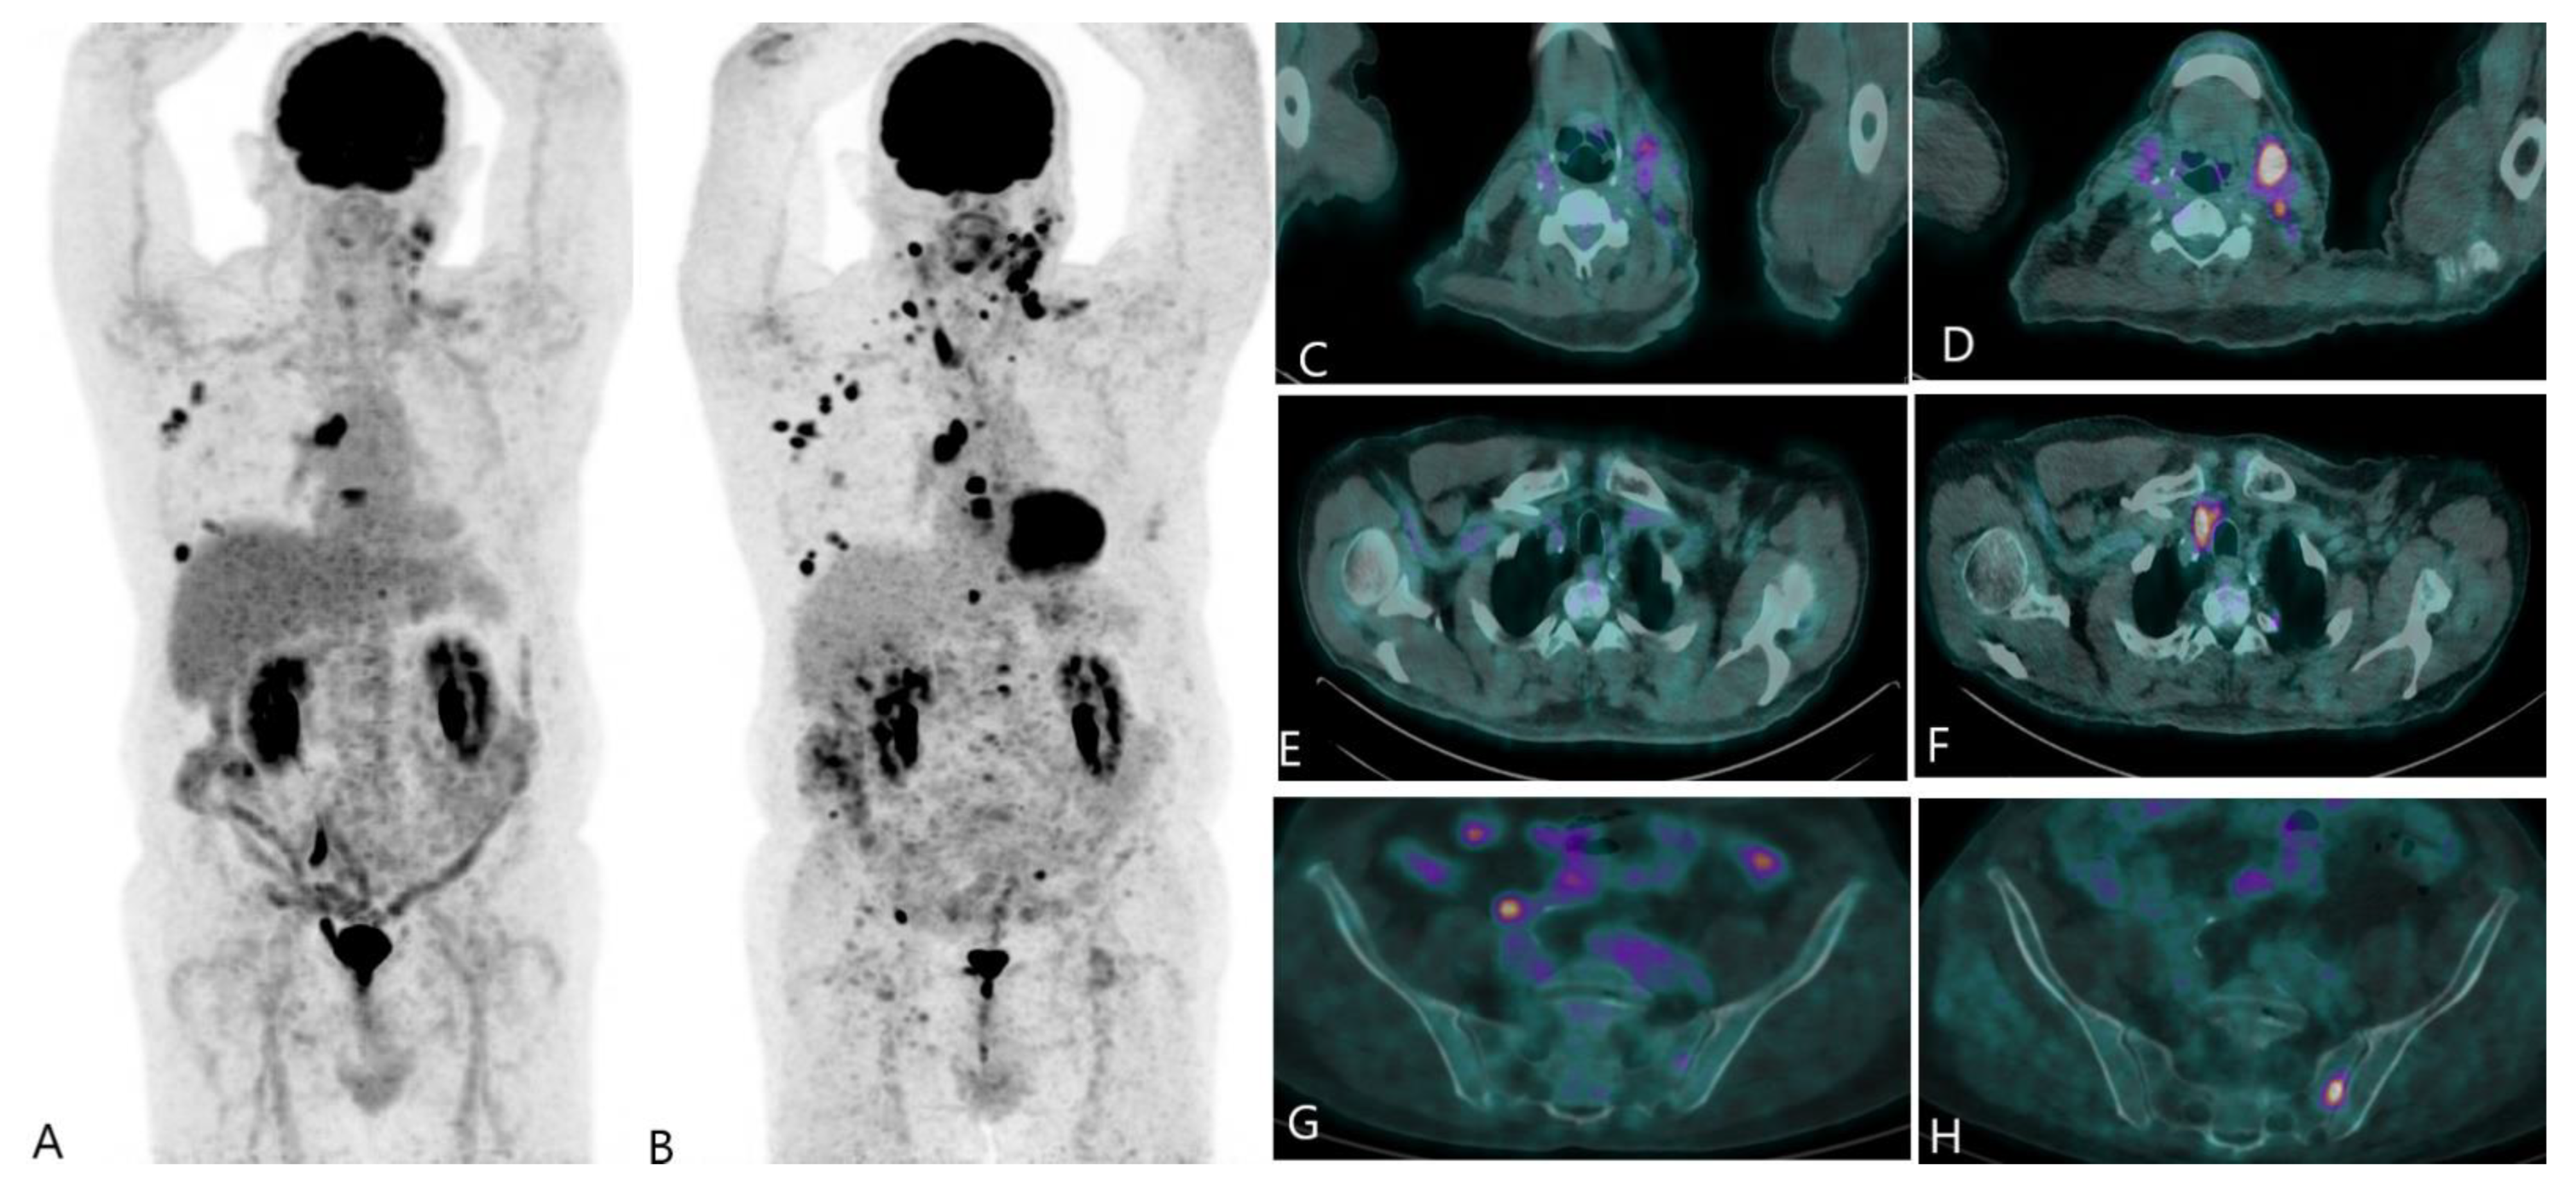

2.2. Recurrent Disease

2.3. Evaluation of Treatment Response